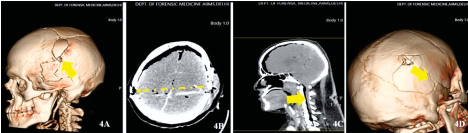

Description: 5A: Entry wound (1,2,3). 5B: Laceration on left occipital region. 5C: Insitu Bullet temporal region. 5D:Fracture of right maxillary sinus. 5E: Exit wound. 5F: Intracranial hemorrhages on the base of skull

Case 3 Virtual Autopsy findings.